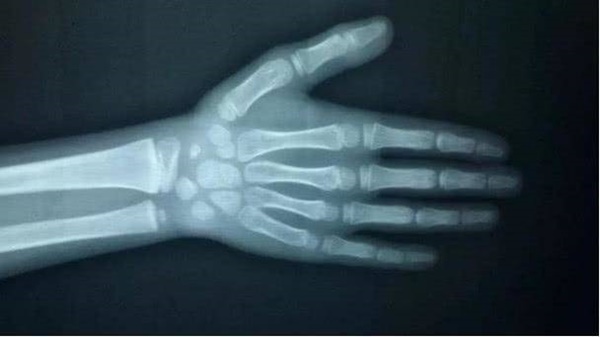

Sau khi nghe lời kể của người mẹ, bác sĩ cho rằng đây không phải là một hiện tượng tốt nên yêu cầu chụp X-quang bàn tay của bé. Kết quả cho thấy tuổi xương của Tingting đã tương đương với trẻ 11 tuổi, hơn 3 tuổi so với tuổi thực của cô bé. Điều đó cho thấy Tingting có dấu hiệu dậy thì sớm trước tuổi. Mặc dù cô bé chỉ cao hơn vài cm so với chiều cao trung bình của trẻ 8 tuổi (1,28m) nhưng lại thấp hơn 12cm so với chiều cao trung bình của trẻ 11 tuổi. Theo dự đoán của bác sĩ, trong tương lai khả năng chiều cao của bé chỉ dưới 1,5m.

Tuổi xương của Tingting bằng tuổi xương của bé 11 tuổi